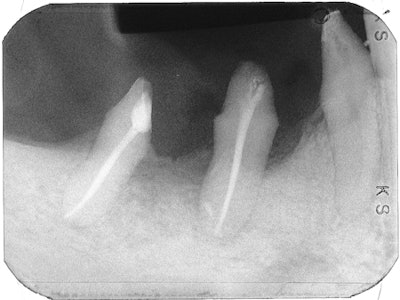

In this case, healing occurred, and a radiograph taken five months later shows resorption of the extruded sealer and healing of the periapical lesion.

A radiograph taken 4.5 years later shows the completed case with bridge in place, bone fill, and the healed periapical lesion.

There was no need for surgery, and once again the roots served as nature's implants.